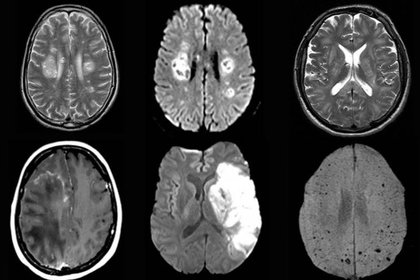

Descenso intensivo vs usual de la tensión arterial en adultos mayores

Una meta de tensión arterial sistólica menor a 130 mmHg no se asoció a cambios en la  movilidad o en las pruebas cognitivas, pero sí a menor progreso de las lesiones subcorticales en la resonancia magnética. Circulation, octubre de 2019